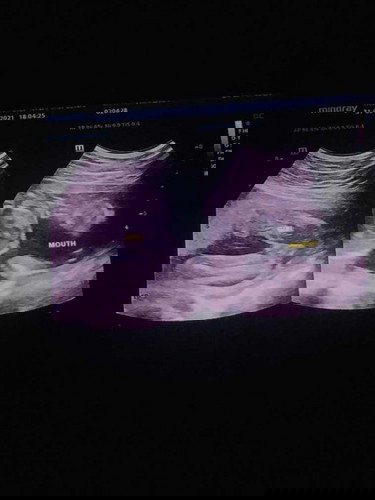

เพื่อนซาวได้หญิง พอคลอดได้ชาย กลัวจะเป็นเหมือนเพื่อนค่ะ เมื่อวานหมอบอกได้หญิง อายุ 22+5 w